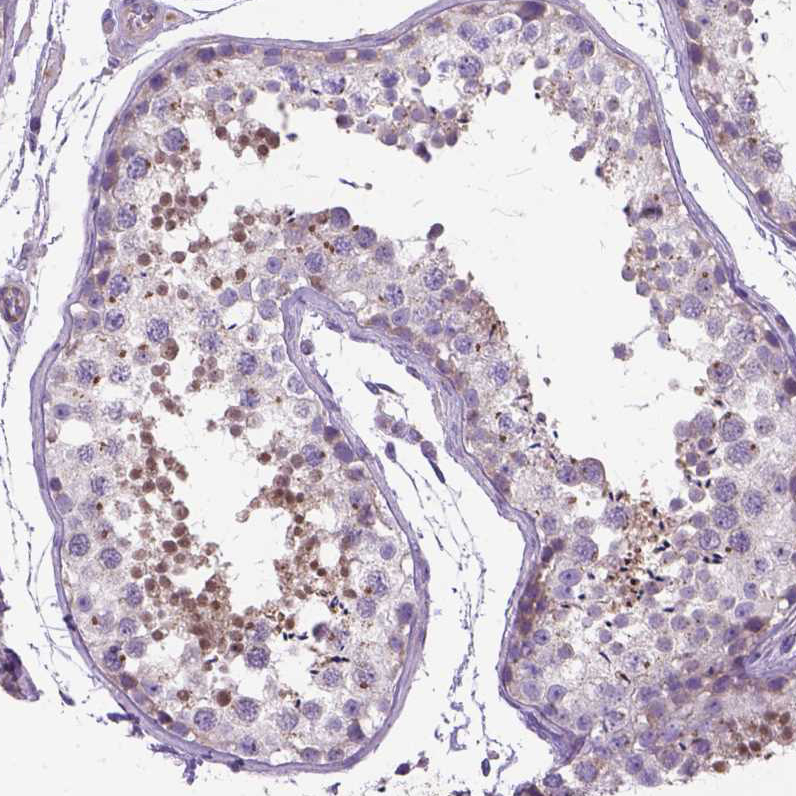

Immunohistochemical staining of human testis shows moderate nuclear positivity in cells in seminiferous ducts.